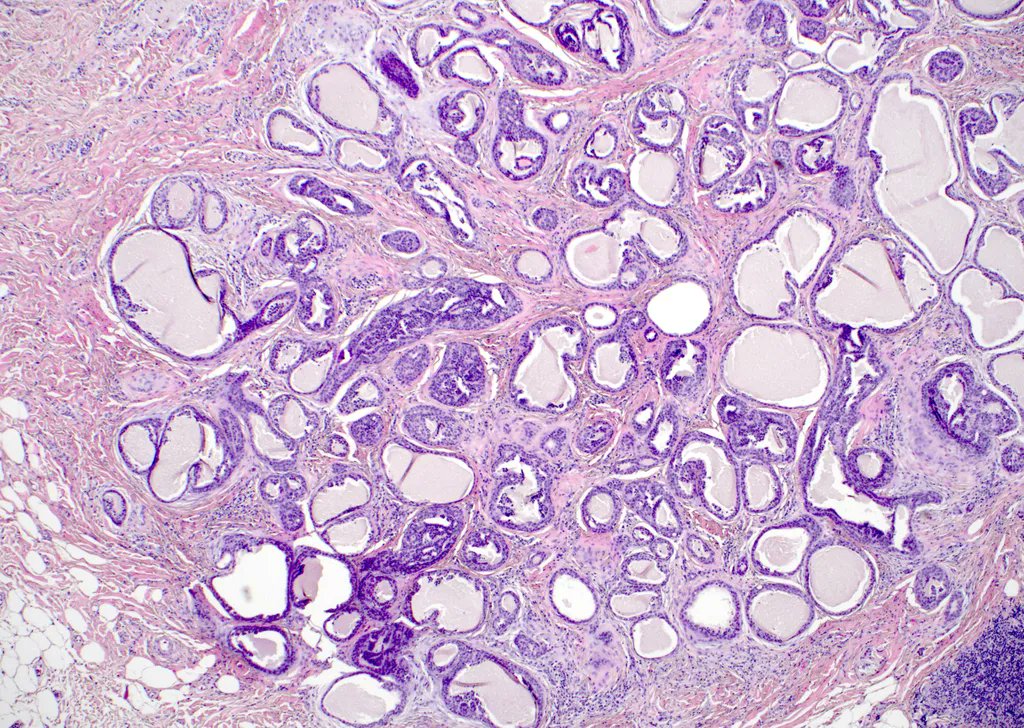

Always a beauty! #dermpath